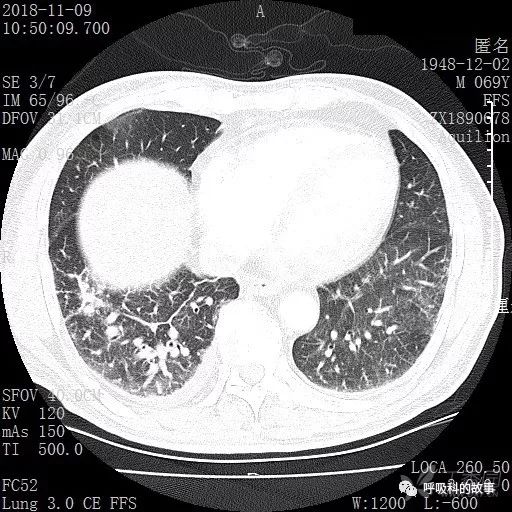

胸部增强CT示右肺门占位伴远端阻塞性肺炎,纵膈、右肺门、右侧颈根部、右侧腋下及肝门部肿大淋巴结。两侧胸腔少量积液。

肺窗CT